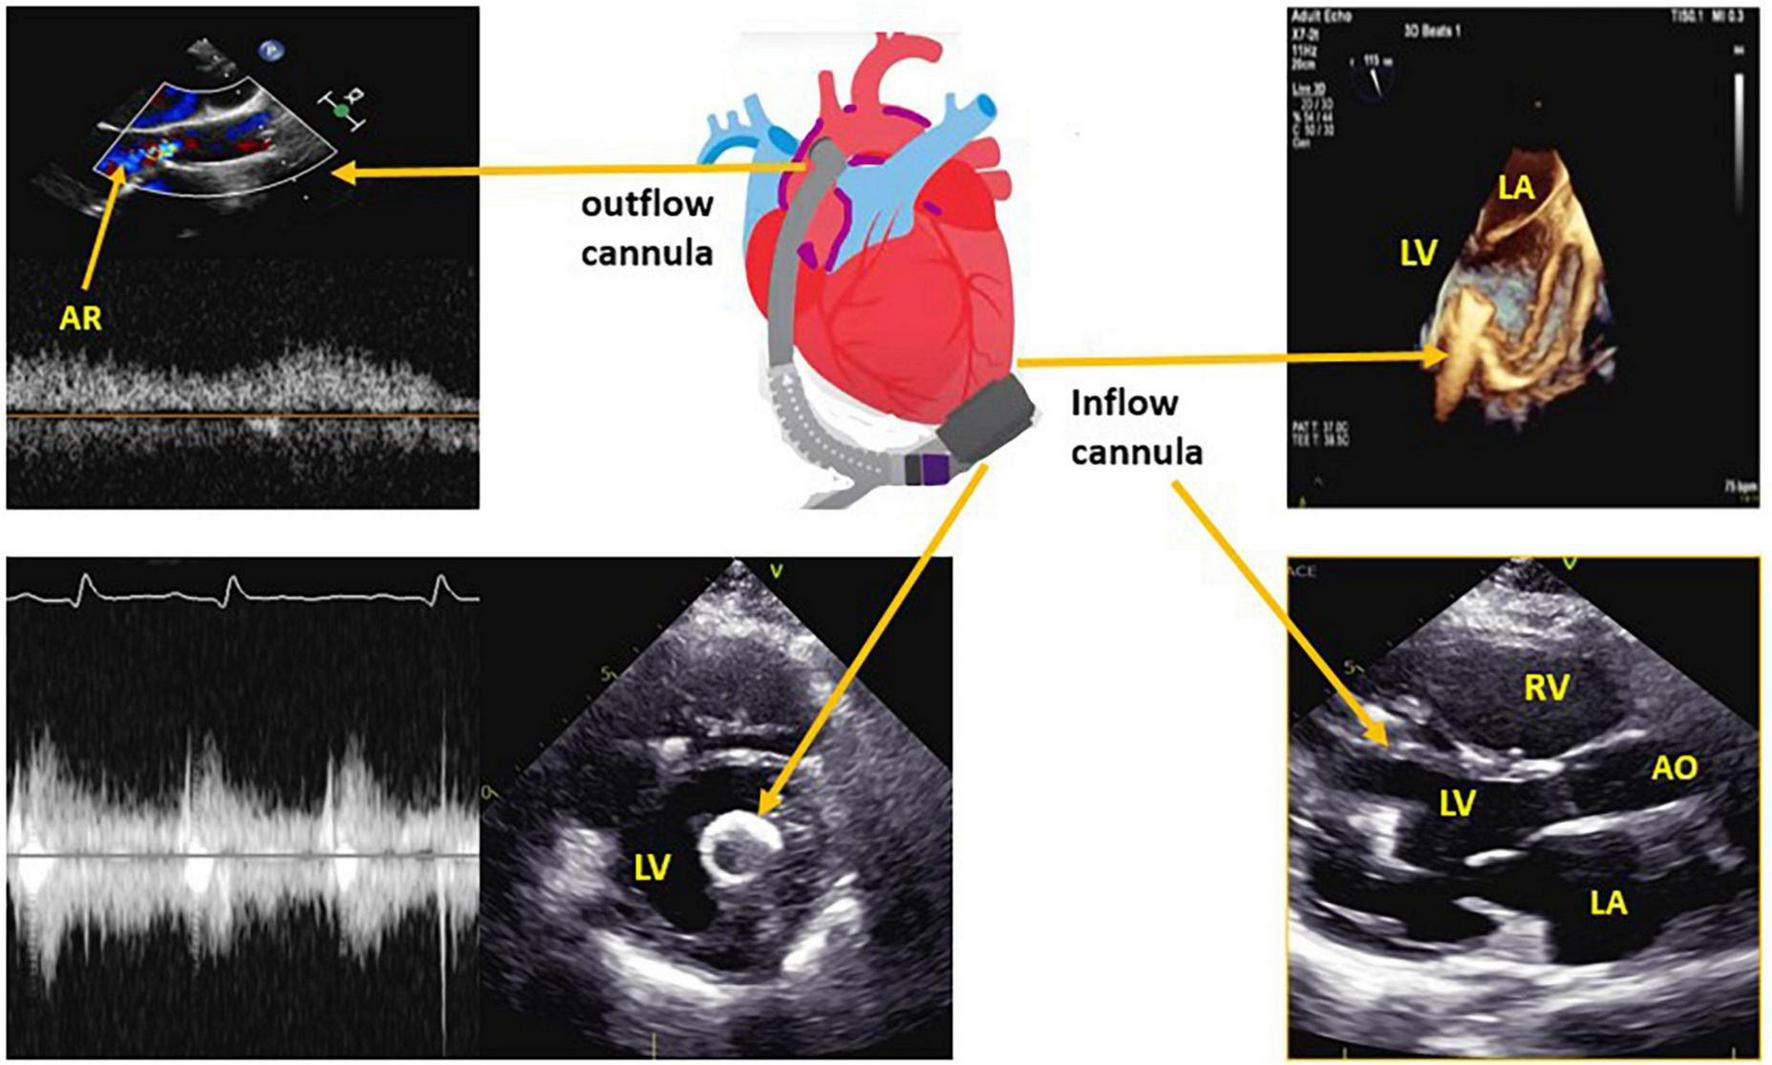

The function of the LVAD is to reduce the workload of the LV by pumping blood via a LV apical cannula to the aorta, to maintain systemic perfusion (Figure 1).

FIGURE 1

Left ventricular assist device (LVAD) structure with the corresponding echocardiographic images for the inflow cannula and outflow cannula. LV, left ventricle; LA, left atrium; RV, right ventricle; AR, aortic regurgitation.